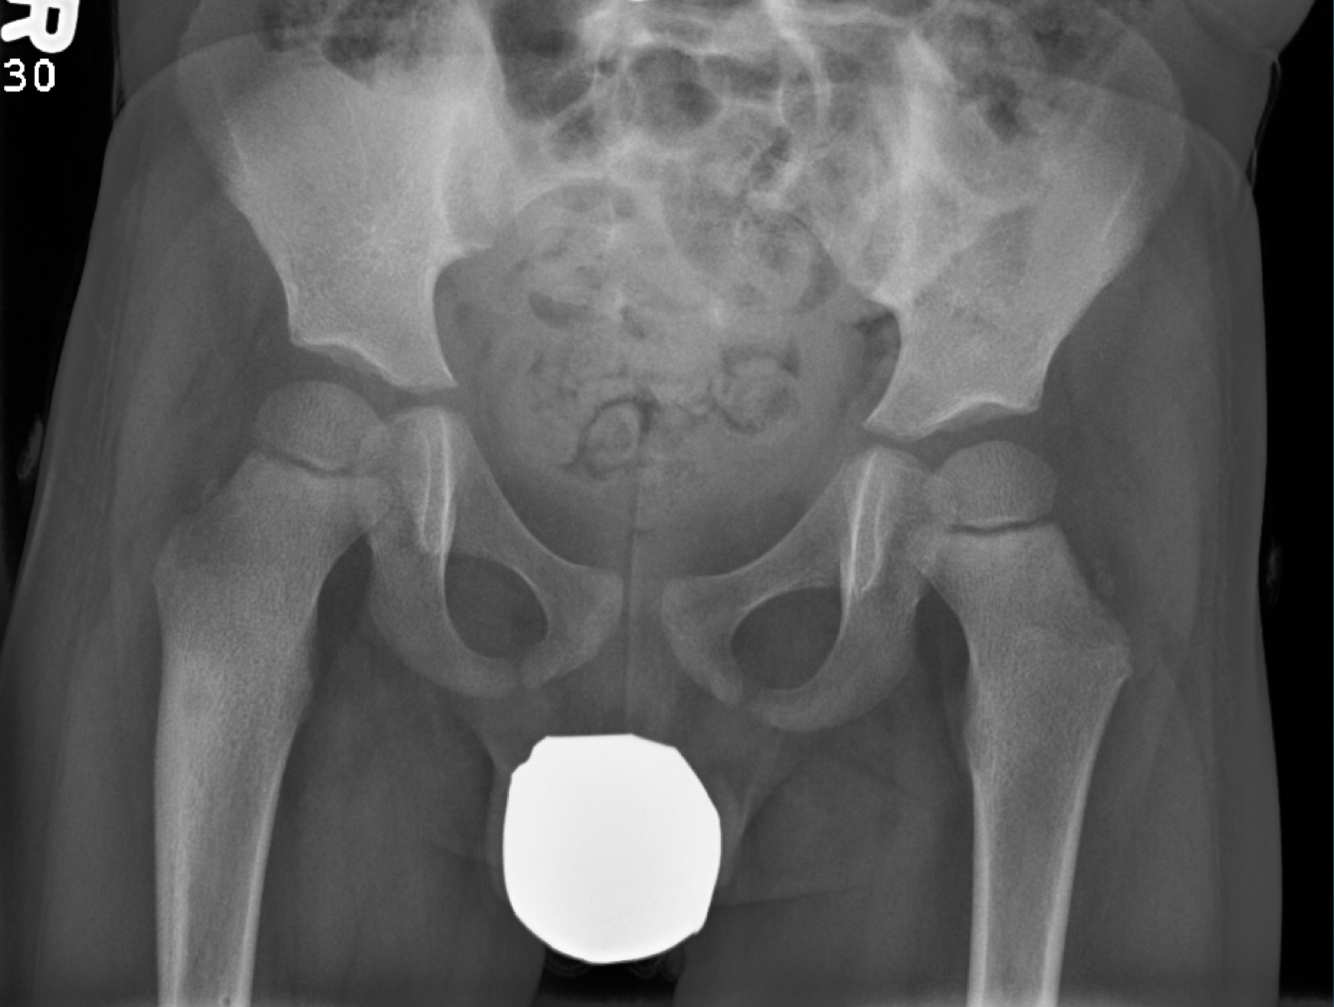

55 YO M Low back pain, insidious onset. Decrease in appetite for the last several months.

50 YO M. Weakness, fatigue, back pain.

Multiple, punched out, osteolytic lesions

think: MM or mets